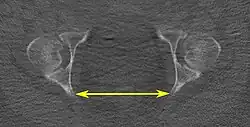

Tomografias computadorizadas de baixa dose em 3D podem ser usadas para estimar os principais parâmetros da pelvimetria:[4]

| Diâmetro intertuberositário |

|

Plano axial |

Os pontos ósseos mais próximos das tuberosidades isquiáticas | 10 a 12 cm.[6] | |